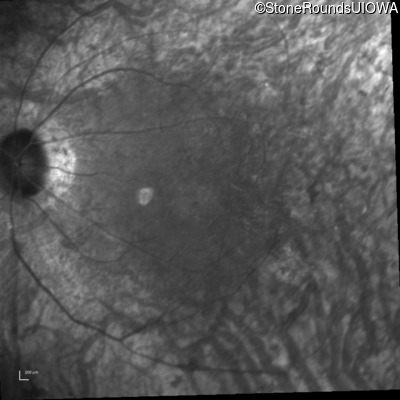

Infrared Fundus Photograph - Right - 20/40 +1

Exemplar